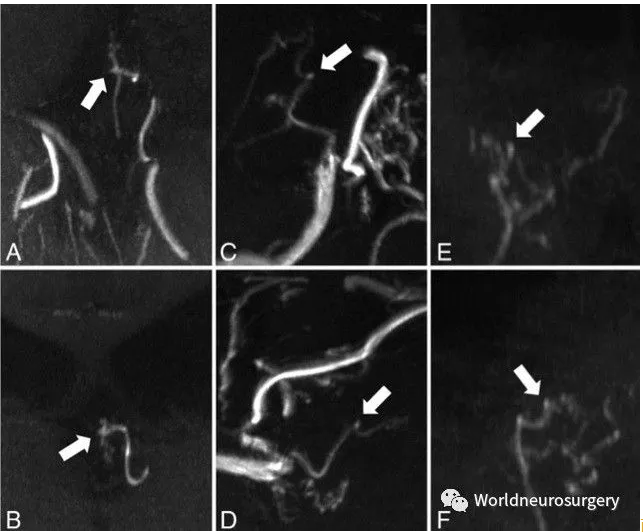

烟雾病(moyamoya病)

7T TOF-MRA能发现传统较低场强磁共振不能发现的微动脉瘤。这对我们了解烟雾病的病理生理机制提供了更多证据。

两个不同的角度观察3个患者的7T磁共振TOF-MRA影像,可以发现脑室内的侧支血管形成了微动脉瘤(箭头所示)